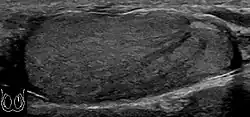

Teratoma Although teratoma is the second most common testicular tumor in children, it affects all age groups. Mature teratoma in children is often benign, but teratoma in adults, regardless of age, should be considered malignant. Teratomas are composed of all three germ cell layers, i.e. endoderm, mesoderm and ectoderm. At ultrasound, teratomas generally form well-circumscribed complex masses. Echogenic foci representing calcification, cartilage, immature bone and fibrosis are commonly seen [Fig. 5]. Cysts are also a common feature and depending on the contents of the cysts i.e. serous, mucoid or keratinous fluid, it may present as anechoic or complex structure [Fig. 6].

Fig. 5. Teratoma. A plaque-like calcification with acoustic shadow is seen in the testis. -